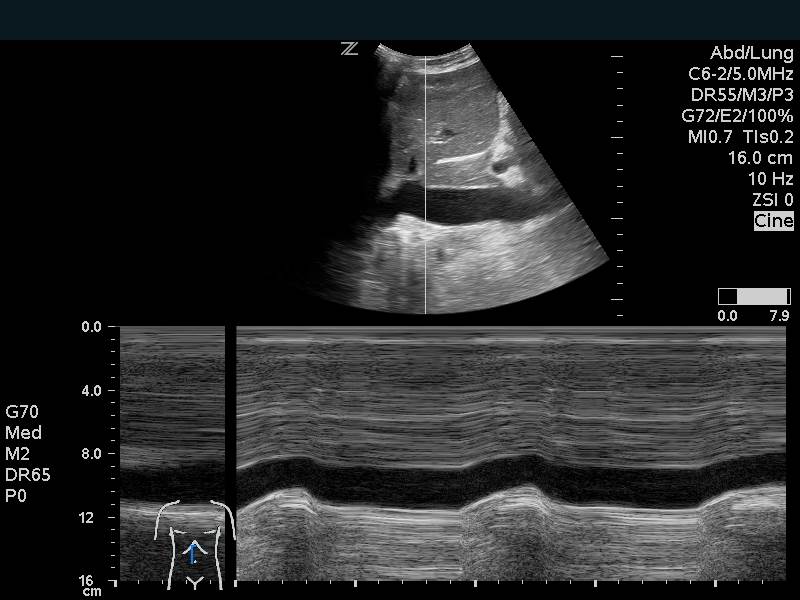

E-point Septal Separation

This is a technique that is commonly employed to provide an objective measurement of systolic function of the left ventricle. Using M-mode, capture the distance between the anterior leaflet of the mitral valve and the interventricular septum. A measure >7mm correlates with reduced cardiac function.13 This measurement may not be accurate in cases of aortic regurgitation, mitral stenosis, hypertrophic cardiomyopathy, and non-sinus rhythm.

Figure 11. Normal E-point septal separation

Figure 12. Inferior Vena Cava Respiratory variation on M-mode